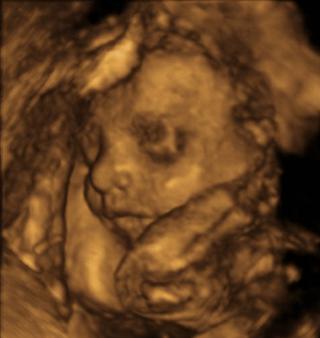

já se musím objednat až budu mít druhý den silnou menstruaci a pak ještě mě čeká 4d vyšetření dělohy.partner se musí objednat na vyšetření spermatu.